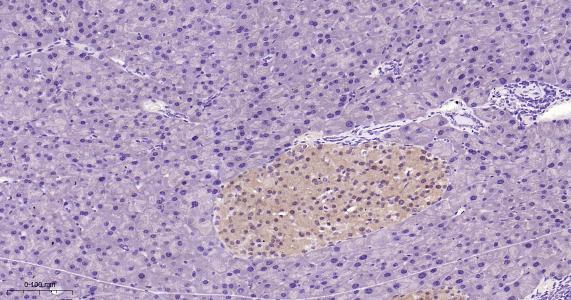

Paraformaldehyde-fixed, paraffin embedded Rat Liver; Antigen retrieval by boiling in sodium citrate buffer (pH6.0) for 15 min; Antibody incubation with TXNRD1 Monoclonal Antibody, Unconjugated(bsm-61558R) at 1:200 overnight at 4°C, followed by conjugation to the bs-0295G-HRP and DAB (C-0010) staining.

Paraformaldehyde-fixed, paraffin embedded Human Pancreas; Antigen retrieval by boiling in sodium citrate buffer (pH6.0) for 15 min; Antibody incubation with TXNRD1 Monoclonal Antibody, Unconjugated(bsm-61558R) at 1:200 overnight at 4°C, followed by conjugation to the bs-0295G-HRP and DAB (C-0010) staining.